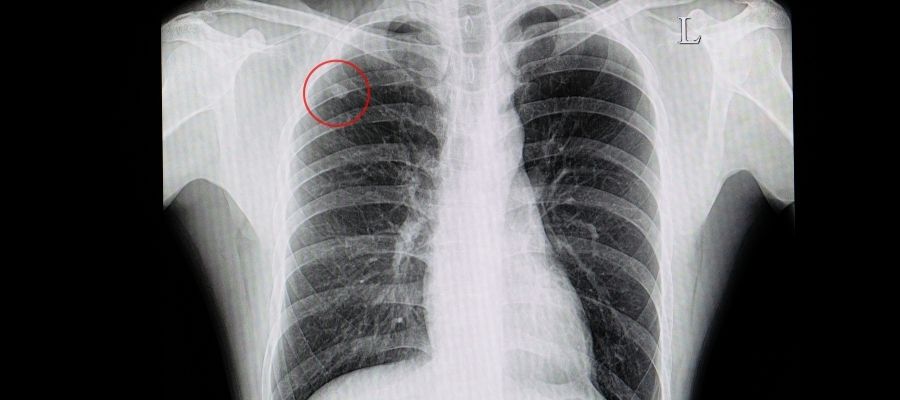

Radyolojik Görüntüleme (BT, Röntgen)

Akciğer nodüllerinin saptanmasında en sık kullanılan yöntem radyolojik görüntülemelerdir.

- Akciğer Röntgeni: Genellikle ilk basamak görüntüleme testi olup, akciğerlerdeki büyük nodülleri saptayabilir. Ancak, küçük nodüller veya diğer yapıların arkasında kalan nodüller röntgende gözden kaçabilir.

- BT (Bilgisayarlı Tomografi): Akciğer nodüllerinin detaylı değerlendirilmesinde kullanılır. BT nodülün boyutunu, şeklini, sınırlarını, yoğunluğunu, iç yapısını ve çevresindeki dokularla ilişkisini çok daha net gösterir. Düşük doz BT taraması, özellikle yüksek riskli bireylerde akciğer kanseri taraması için önerilmektedir.